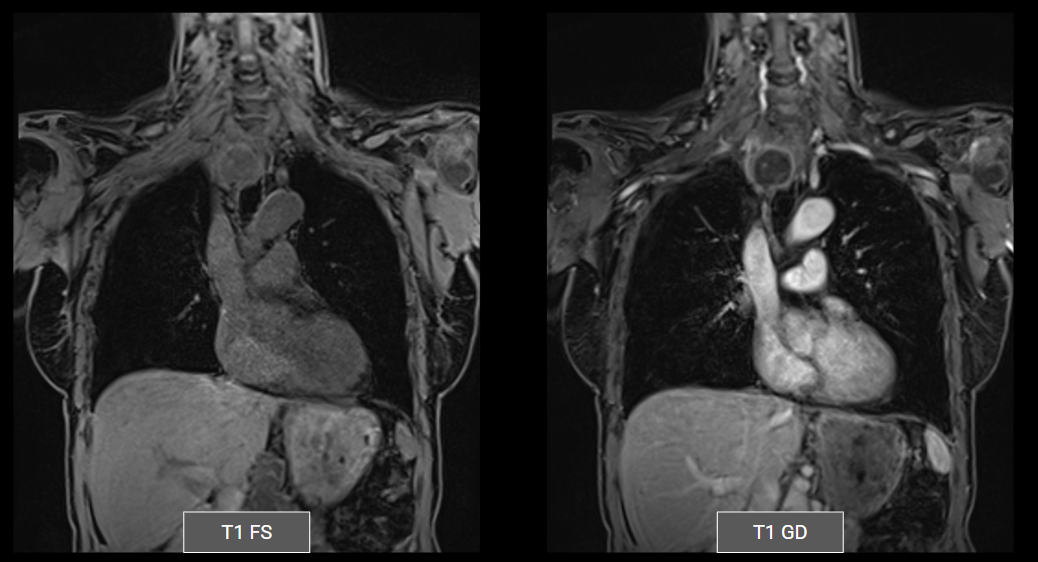

Ressonância do mediastino: